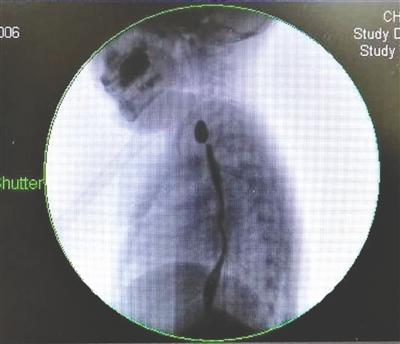

女童彤彤误吞纽扣电池,食道被烧伤

今年6月初,她的食道内取出一枚和1角硬币大小相近的纽扣电池,电池中漏出的强碱性液体致使她的食道被烧伤,全食道僵硬,出现食道疤痕性狭窄,几乎丧失功能。

重庆医科大学附属儿童医院胸心外科副主任李勇刚介绍,彤彤的食道是被纽扣电池漏出的强碱性液体烧伤。尽管到该院时电池已被取出,但因食道被烧伤,彤彤的全食道已经僵硬,几乎丧失功能,只能进食流质物。这是因为,彤彤的食道出现了疤痕性狭窄,食道最狭窄处宽度仅有1.5毫米,而正常人的食道宽约2厘米。

李勇刚介绍,彤彤到儿童医院接受治疗后,医院对其进行了3次食道扩张手术,但每次扩张后仅几天便出现收缩,效果不佳。9月12日,医院为彤彤实施了食道支架置入手术,在她的食道内置入了全覆膜食管支架,使得食管腔明显增大。如顺利,6个月后,该支架将取出。